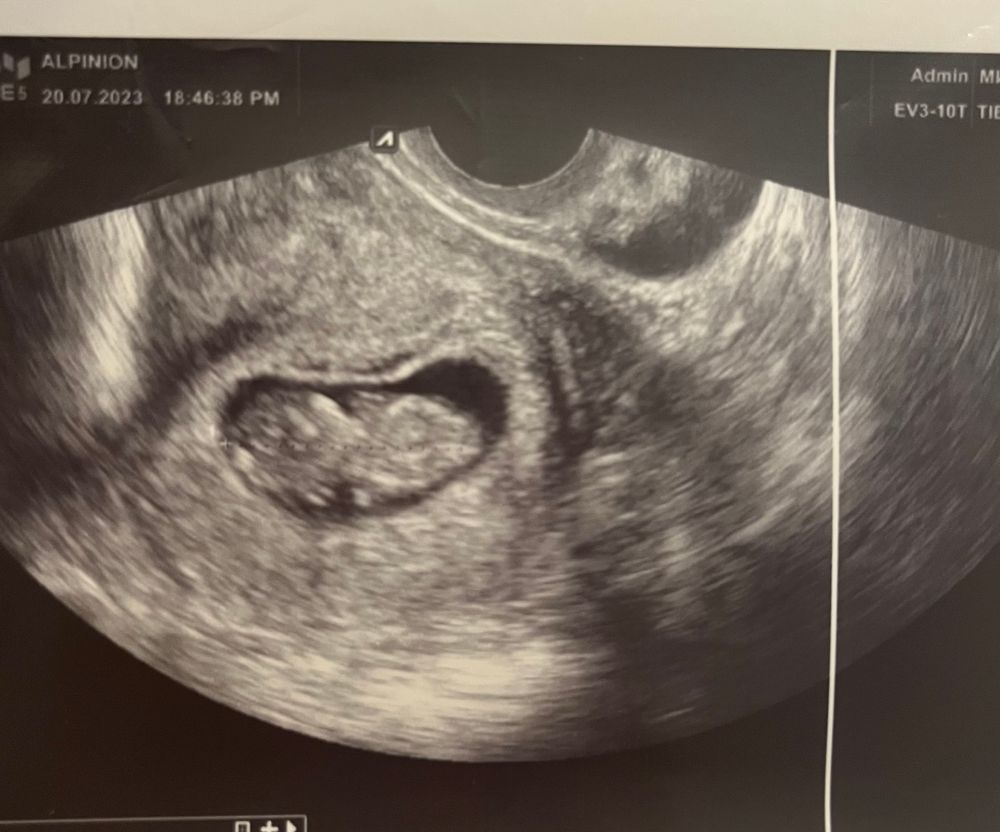

Наша Бусинка❤️КТР 2,87. ЧСС 168. Ставят угрозу из-за тонуса по передней стенке, предложили лечь в стационар, но решила что отлежусь недельку дома. Я так понимаю, что явление это распространенное. И вот как из-за этого не беспокоится?